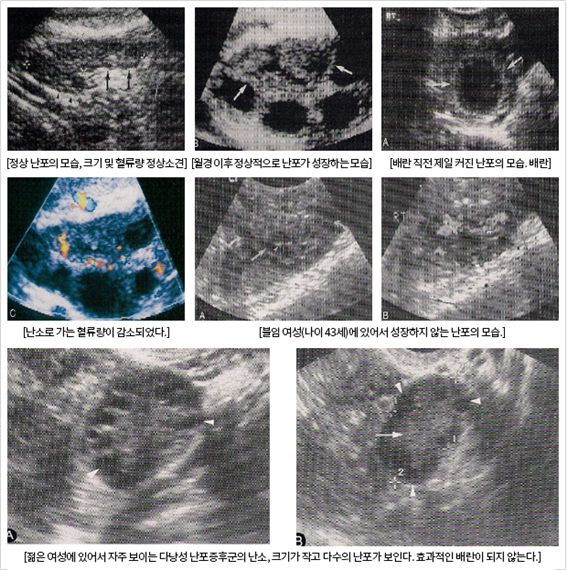

³­¼Ò±â´É°Ë»ç

¿©¼ºÀÌ ³ªÀ̰¡ µé¾î°¨¿¡ µû¶ó ³­¼Ò¿¡ ³²¾ÆÀÖ´Â ³­Àڵ鵵 ³ëÈ­ÇÏ°Ô µË´Ï´Ù. À̰ÍÀº ³­ÀÚ°¡ Á¤ÀÚ¿Í ¼öÁ¤ÇÒ ¼ö ÀÖ´Â ´É·ÂÀÌ ¶³¾îÁø´Ù´Â °ÍÀ» ÀǹÌÇÕ´Ï´Ù. ³­ÀÚÀÇ ¼ö°¡ °¨¼ÒÇÏ´Â °Í°ú µ¿½Ã¿¡ ÁúÀÌ ÀúÇÏµÈ ³­ÀÚÀÇ ¼ö°¡ Áõ°¡Çϸ鼭, žÆÀÇ ¿°»öü ÀÌ»óÀÌ ¹ß»ýÇÒ À§Ç輺ÀÌ ³ô¾ÆÁý´Ï´Ù.

30¼¼ ÀÌÇÏÀÇ ¿©¼ºÀÌ ÀÓ½ÅÀ» ½ÃµµÇÒ ¶§ ÇÑ´Þ Áß ÀÚ¿¬ÀÓ½ÅÀÌ µÉ °¡´É¼ºÀº Æò±ÕÀûÀ¸·Î ¾à 20%ÀÌÁö¸¸, 40¼¼ ÀÌ»óÀÇ ¿©¼ºÀÌ ÀÓ½ÅÇÒ °¡´É¼ºÀº ¾à 5%·Î Ãß»êµÇ°í ÀÖ½À´Ï´Ù.

AMH(Anti mullerian hormone)¶õ?

¿©¼ºÀÇ AMH´Â Ãâ»ý½Ã¿¡´Â ÀûÀº ¾çÀ» ºÐºñÇÏ´Ù°¡ °¡ÀÓ±â Ãʱ⿡ °¡Àå ¸¹Àº ¾çÀ» ºÐºñÇϰí Áö¼ÓÀûÀ¸·Î °¨¼ÒµÇ¾î Æó°æÀÌÈÄ¿¡ °ËÃâµÇÁö ¾Ê¾Æ ³­¼Ò±â´É°ú ¹ÐÁ¢ÇÑ °ü·ÃÀ» º¸ÀÌ´Â °ÍÀ¸·Î ¾Ë·ÁÁ® ÀÖ½À´Ï´Ù.

»ý¸®ºÒ¼øÀÎ °æ¿ì

»ý¸®°¡ ¿øÈ°ÇÏÁö ¾ÊÀ» °æ¿ì¿¡´Â ¹è¶õÀÌ Àß µÇ´ÂÁö¸¦ °Ë»çÇØ º¸¾Æ¾ß ÇÕ´Ï´Ù. »ý½Ä¿¡ °ü·ÃµÈ ÁÖ¿ä È£¸£¸óÀ¸·Î Ȳü È£¸£¸ó°ú ³­Æ÷ È£¸£¸óÀÌ Àִµ¥ ¹è¶õÀÌ Àß ¾ÈµÇ´Â °æ¿ì¿¡´Â ³­Æ÷ È£¸£¸ó¸¸ ºÐºñµÇ¾î °ú´ÙÇÑ ³­Æ÷ È£¸£¸óÀ¸·Î ÀÎÇØ ºÒÀÓÀ̳ª ¾Ï¿¡ À̸£´Â °æ¿ìµµ ÀÖ½À´Ï´Ù.

»ý¸®ºÒ¼øÀÎ °æ¿ì¿¡´Â ¹è¶õ À¯¹«¸¦ È®ÀÎÇØ¾ß ÇÏ¸ç °Ë»ç¹ýÀ¸·Î´Â ±âÃÊ Ã¼¿Â¹ý, ÀڱðæºÎ Á¡¾×°Ë»ç, ÃÊÀ½ÆÄ °Ë»ç, Àڱ󻸷 °Ë»ç, ³úÇϼöü È£¸£¸ó °Ë»ç µîÀÌ ÀÖ½À´Ï´Ù.